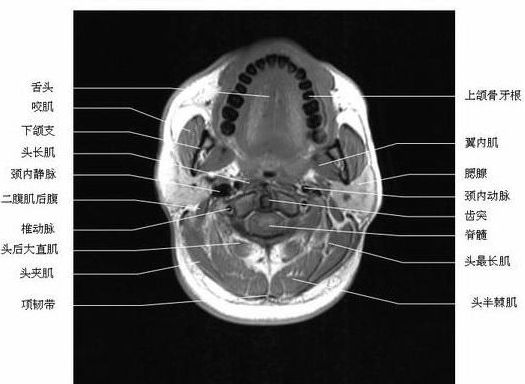

头颈部横断面-磁共振

头颈部横断面-MRI